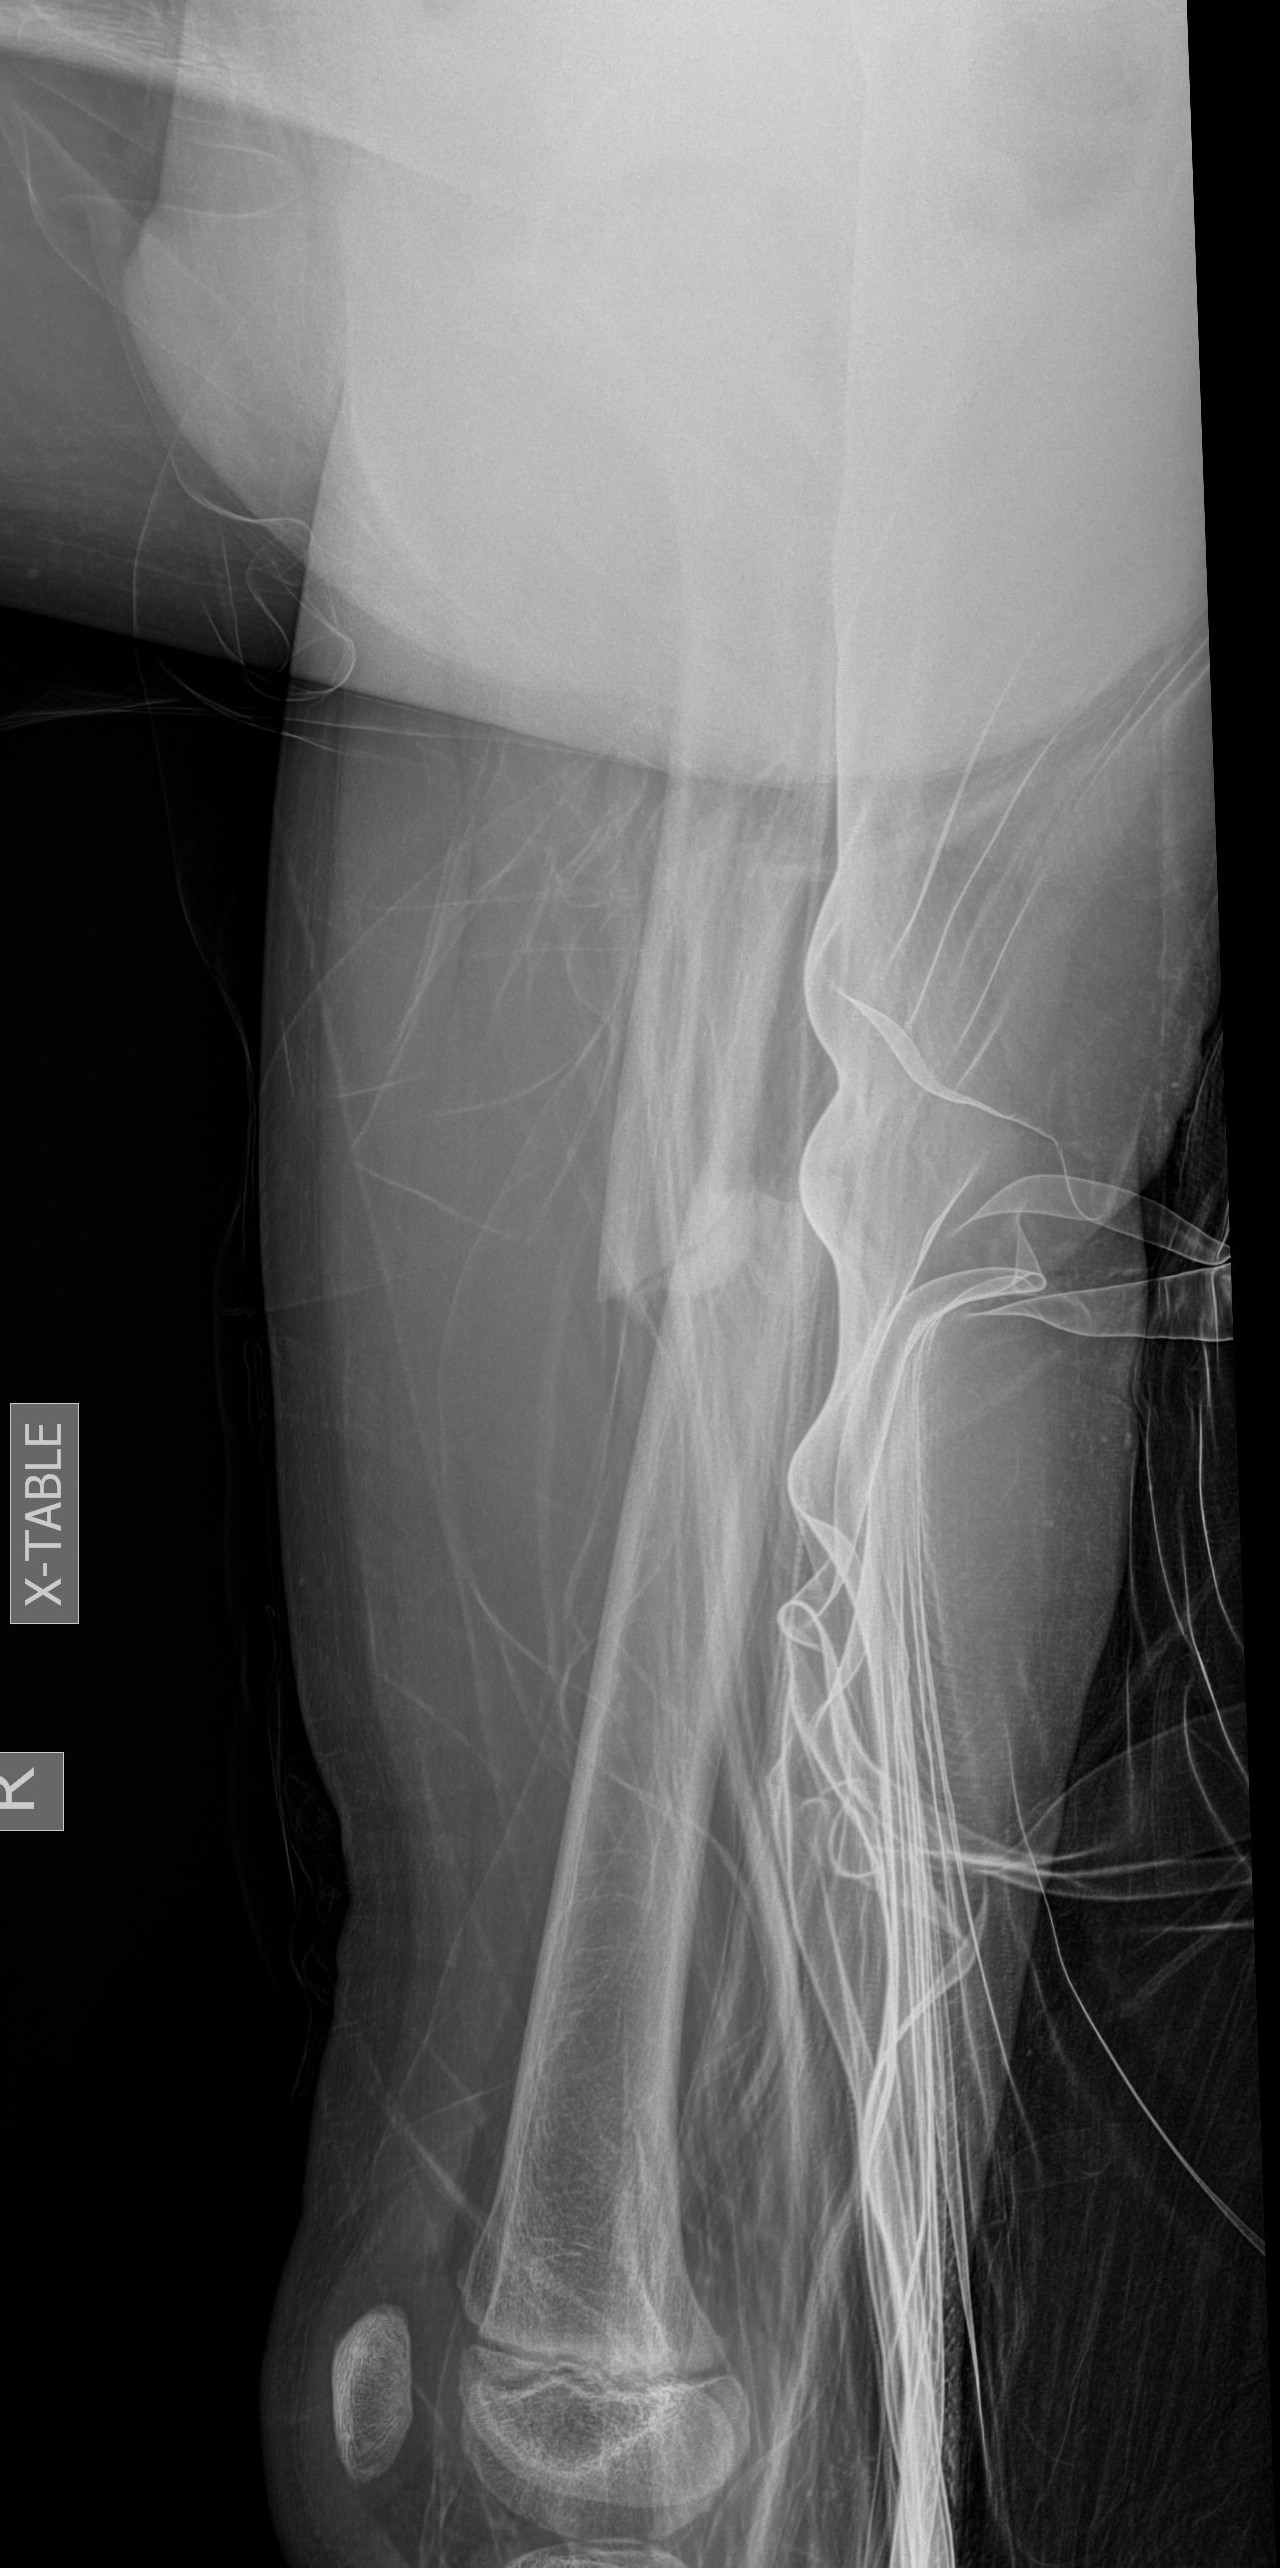

Flexible nails / Titantium Elastic Nails

Indications

Length stable fractures i.e simple transverse, short oblique

Midshaft fractures

Maximum weight up to 50 kg / 12 years old

Wires

- available 1. 5 mm - 4.0 mm

- 30 - 40% of diameter of diaphyseal medullary canal

- i.e. if canal 10 mm wide, use 2 x 4 mm

- recommend using 2 wires same diameter to avoid rotational instability

Entry points

- medial and lateral insertion

- 1 - 2 cm proximal to distal femoral physis

Wire passage

- bend wire for 3 point fixation with bend at fracture site

- also bend the tip of the wire

- medial entry wire will pass into femoral neck

- lateral wire will pass into greater trochanter / medial wire into femoral neck

Acceptable alignment

- 10o varus / valgus

- 15o flexion / extension

- 15 mm shortening